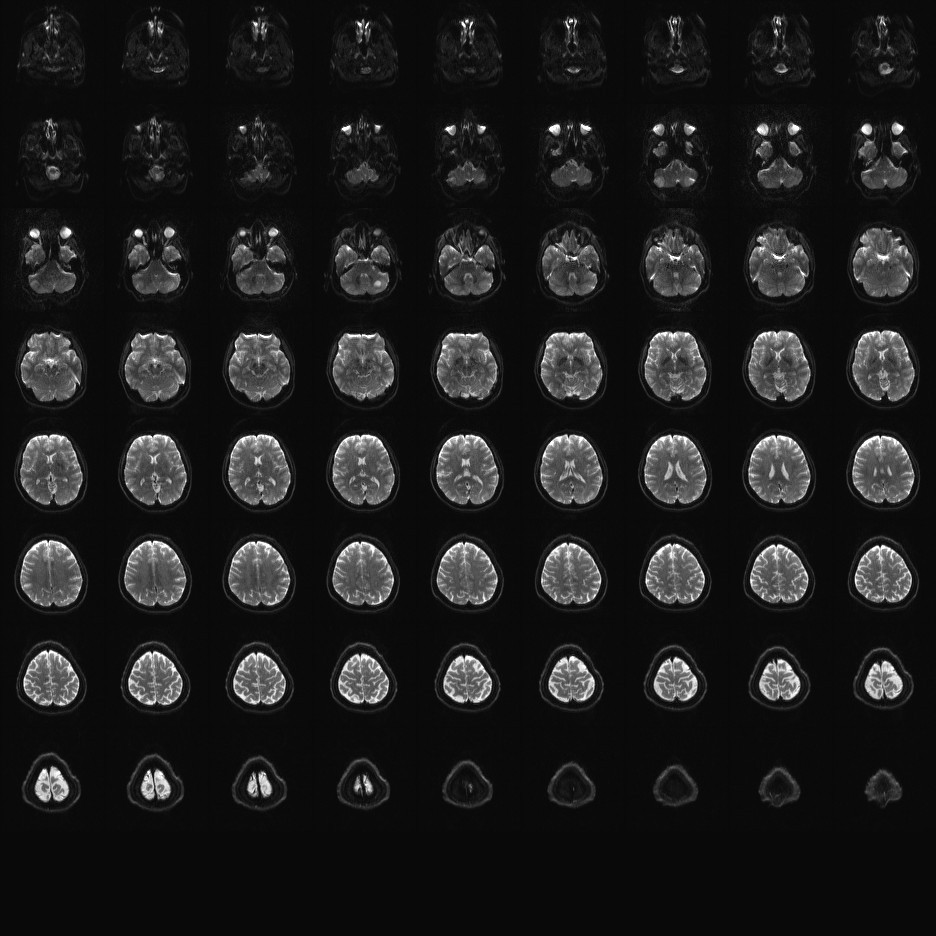

Multi-banded RF pulses can be used to accelerate volume coverage along the slice direction by simultaneously exciting and acquiring multiple slices and subsequently unaliasing them using parallel imaging principles and the spatial information available in multi-channel RF array coils.

This allows for a direct reduction in the volume TR by the number of simultaneously excited slices (i.e., the multiband (MB) factor or the slice acceleration factor).